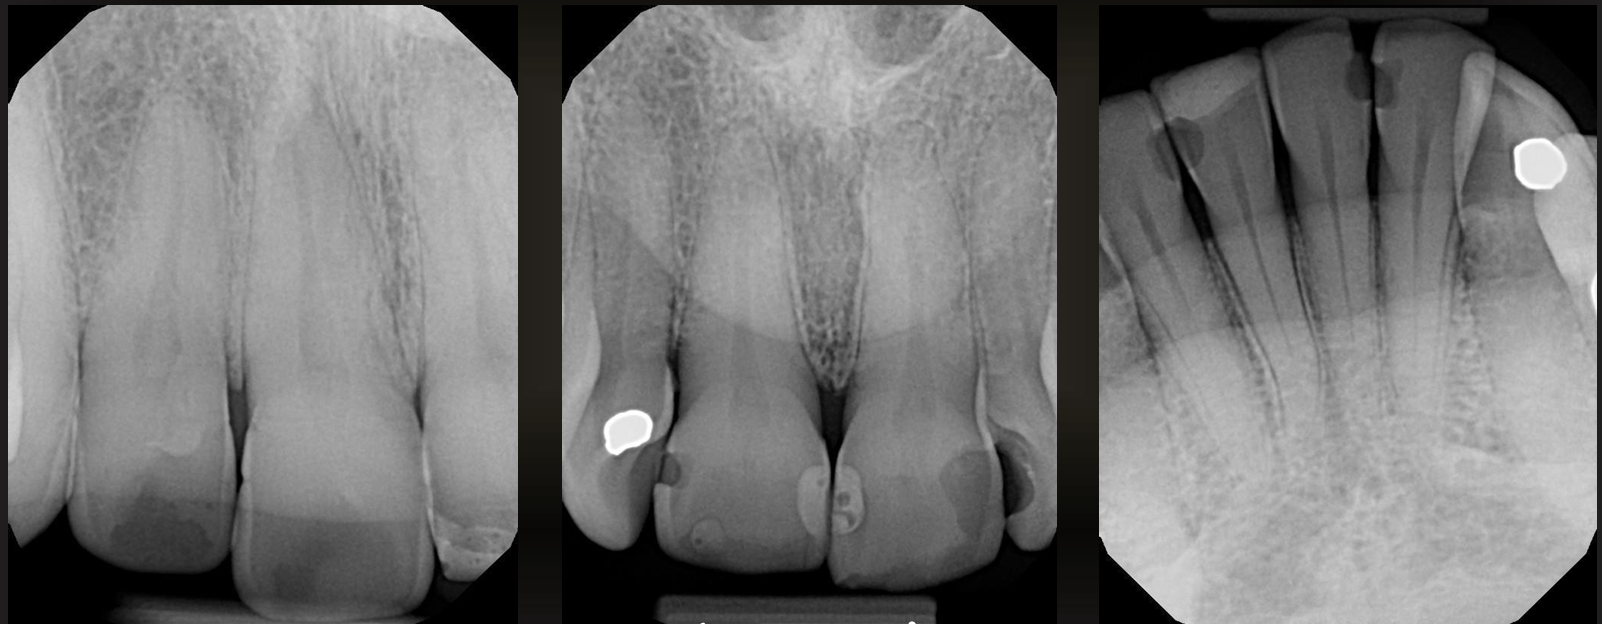

recurrent caries

around the margin of existing restorations, spreads in a natural way

what do these images have?

what are these arrows pointing at?

a restoration with a radiolucent liner- the box is too sharply defined to be a natural process (like secondary caries)